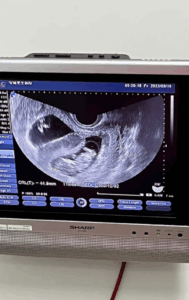

そして妊娠を諦めそうになったとき、双子の赤ちゃんを授かることができた投稿者さん夫婦。

何度か流産を経験していたこともあり、妊娠が分かったときは嬉しさと同時に、無事に出産まで辿り着けるかという不安があったそうです。出産後、双子の赤ちゃんに初めて会ったときも、自分たちの子どもが無事に生まれたことが半分信じられなかったといいます。